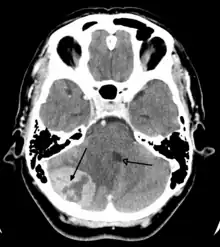

Imaging

Medical imaging plays a central role in the diagnosis of brain tumors. Early imaging methods – invasive and sometimes dangerous – such as pneumoencephalography and cerebral angiography have been abandoned in favor of non-invasive, high-resolution techniques, especially magnetic resonance imaging (MRI) and computed tomography (CT) scans, though MRI is typically the reference standard used.[37] Neoplasms will often show as differently colored masses (also referred to as processes) in CT or MRI results.

- Benign brain tumors often show up as hypodense (darker than brain tissue) mass lesions on CT scans. On MRI, they appear either hypodense or isointense (same intensity as brain tissue) on T1-weighted scans, or hyperintense (brighter than brain tissue) on T2-weighted MRI, although the appearance is variable.

- Contrast agent uptake, sometimes in characteristic patterns, can be demonstrated on either CT or MRI scans in most malignant primary and metastatic brain tumors.

- Pressure areas where the brain tissue has been compressed by a tumor also appear hyperintense on T2-weighted scans and might indicate the presence a diffuse neoplasm due to an unclear outline. Swelling around the tumor known as peritumoral edema can also show a similar result.

This is because these tumors disrupt the normal functioning of the BBB and lead to an increase in its permeability. More recently, advancements have been made to increase the utility of MRI in providing physiological data that can help to inform diagnosis and prognosis. Perfusion Weighted Imaging (PWI) and Diffusion Weighted Imaging (DWI) are two MRI techniques that reviews have been shown to be useful in classifying tumors by grade, which was not previously viable using only structural imaging.[38] However, these techniques cannot alone diagnose high- versus low-grade gliomas, and thus the definitive diagnosis of brain tumor should only be confirmed by histological examination of tumor tissue samples obtained either by means of brain biopsy or open surgery. The histological examination is essential for determining the appropriate treatment and the correct prognosis. This examination, performed by a pathologist, typically has three stages: interoperative examination of fresh tissue, preliminary microscopic examination of prepared tissues, and follow-up examination of prepared tissues after immunohistochemical staining or genetic analysis.